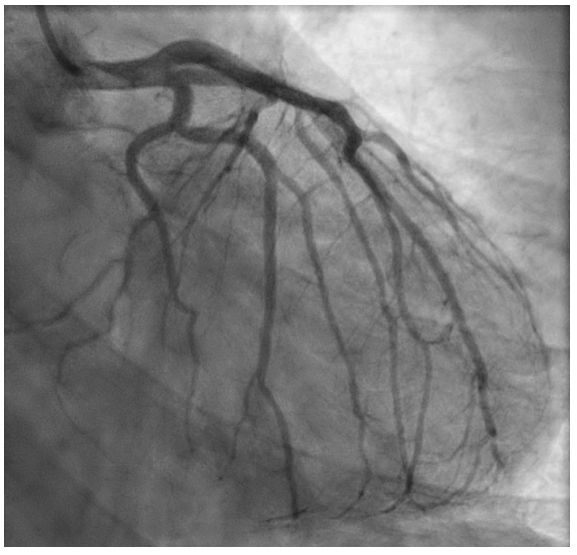

病史摘要:48岁男性患者,2025年10月24日9:40工作时突发意识丧失、小便失禁、呕吐。3年前曾行PCI术,高血压、糖尿病用药不详。 诊疗过程:入院查体神情萎靡、神志模糊等,血压低。心电图提示STEMI,实验室检查多项指标异常。西医诊断为急性前壁高侧壁心肌梗死合并心源性休克(Killip IV级)等,中医诊断为卒心痛(气虚血瘀证)。11:08行冠状动脉造影,对前降支病变处理,术中患